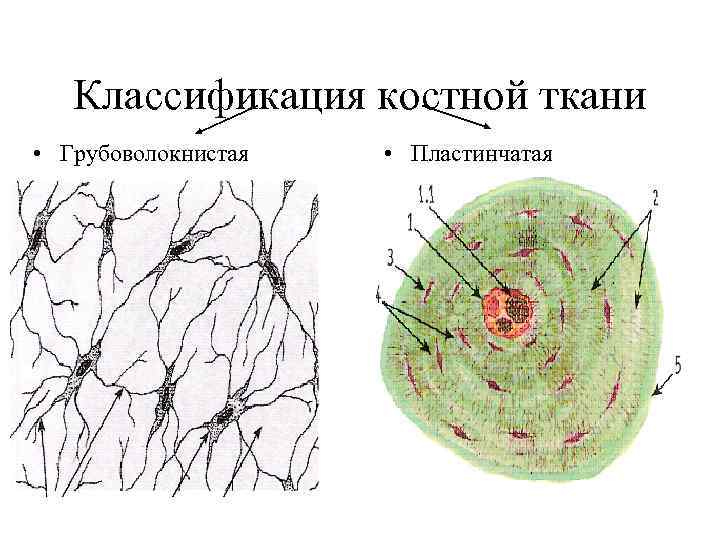

Структура грубоволокнистой костной ткани: наглядные примеры